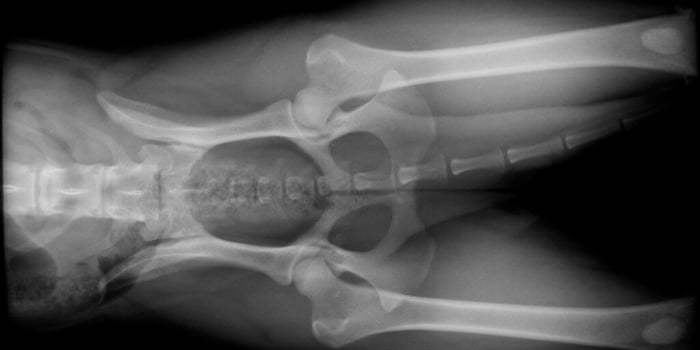

PennHIP measures the actual amount of passive laxity in the hip joint. It accurately predicts whether a puppy will develop hip dysplasia. PennHIP views place a standard force on the hips to see how far the ball comes out of the socket (laxity of the joint). This allows for a calculation of a distraction index (DI), which is a measure of hip laxity.

PennHIP consists of three separate radiographs:

- Distraction view: Allows for quantitative measurements of hip joint laxity

- Compression view: Obtains hip joint congruity readings

- Standard hip-extended view: Evaluates for any OA changes

These X-rays are of the same dog. As you can see, the distraction view shows much more laxity in the hips than the standard hip-extended view.